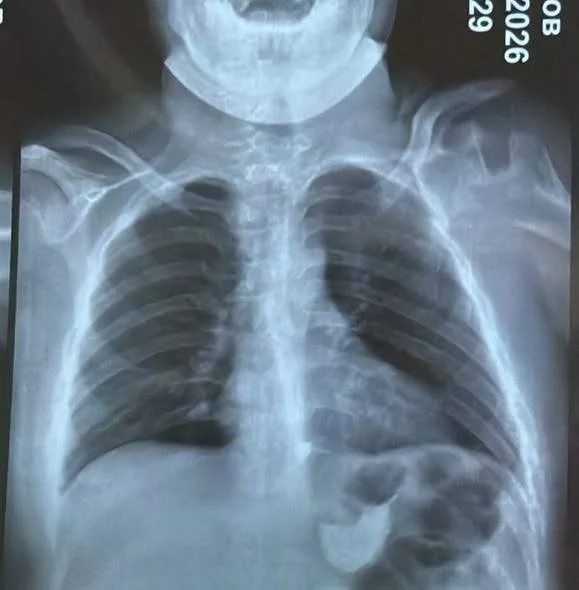

Бишкек, 02.04.26. /Кабар/. Бишкекте 15 жаштагы өспүрүм сөөк жутуп алып, ал кызыл өңгөчүнө тыгылып калган. Бул тууралуу Бишкек шаардык балдардын тез жардам клиникалык ооруканасынан билдиришти.

Маалыматка ылайык, бала 4 сантиметр өлчөмүндөгү сөөктү жутуп алган. Шаардагы эки ооруканада сөөктү чыгара алышпагандыктан, өспүрүм Бишкек шаардык балдардын тез жардам клиникалык ооруканасына жеткирилген.

"Дарыгерлер ыкчам түрдө операция жасап, тыгылып калган сөөктү ийгиликтүү алып чыгышты. Оор абалда келген балага дароо керектүү медициналык жардам көрсөтүлүп, операция жасалды", — деп белгилешти ооруканадан.